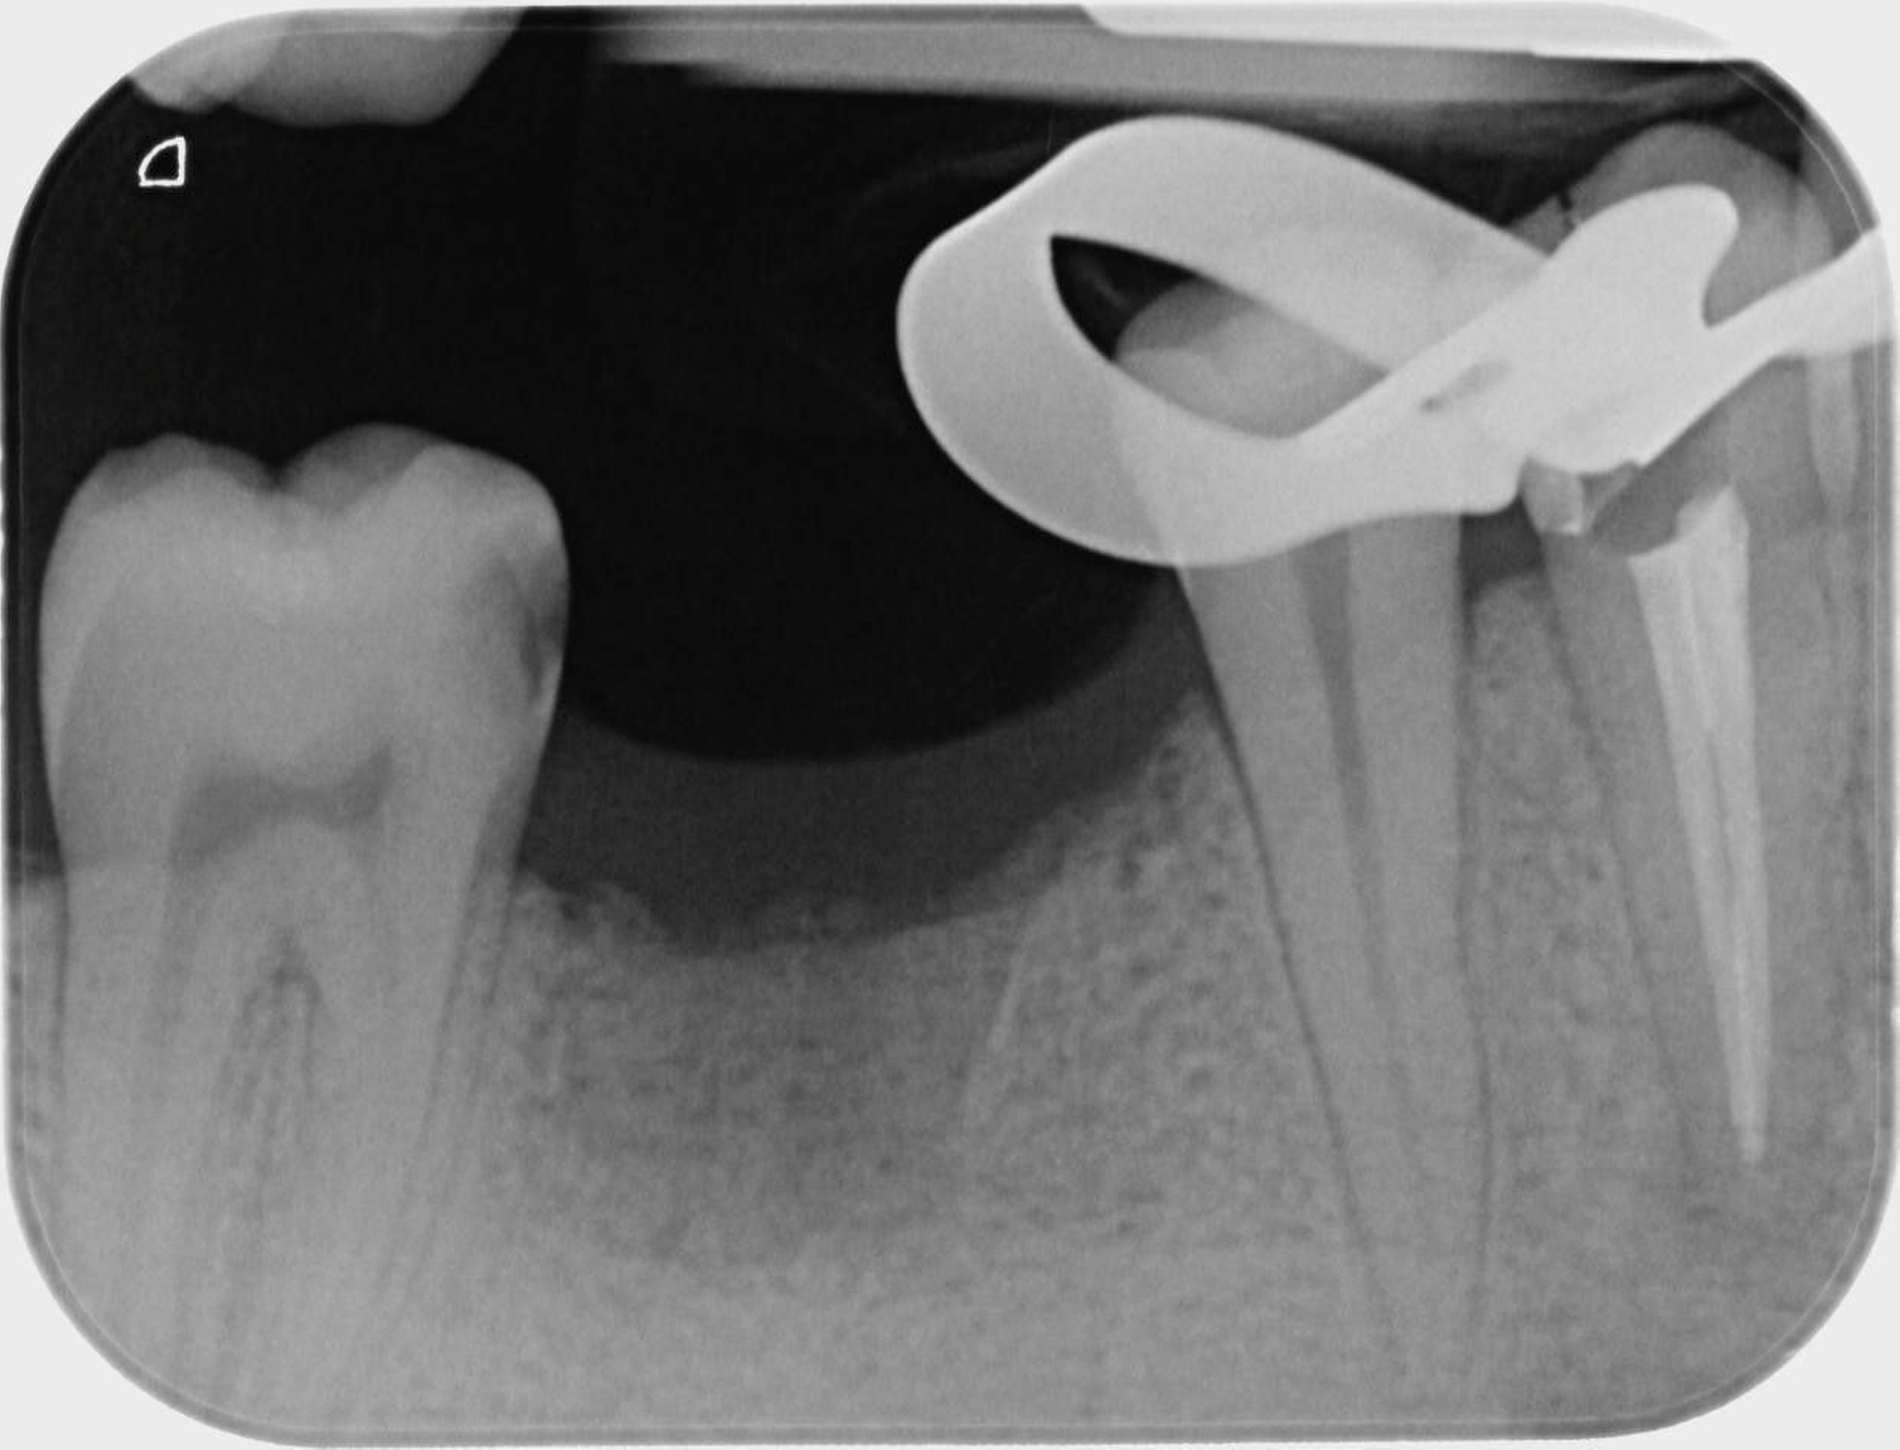

Die Wurzelkanalbehandlungen der Preisträgerer wurden als exzellent eingestuft, da sie einen besonders hohen Schwierigkeitsgrad aufwiesen. Dazu gehören schwierige Ausgangssituationen, etwa bei Durchführung einer Wurzelkanalrevision, bei der eine bereits vorhandene Wurzelkanalbehandlung revidiert werden muss. Auch anatomische Besonderheiten, wie zwei Wurzelkanäle in einer Wurzel, stellen eine besondere Herausforderung dar und bedürfen einer besonders aufwendigen Behandlung.